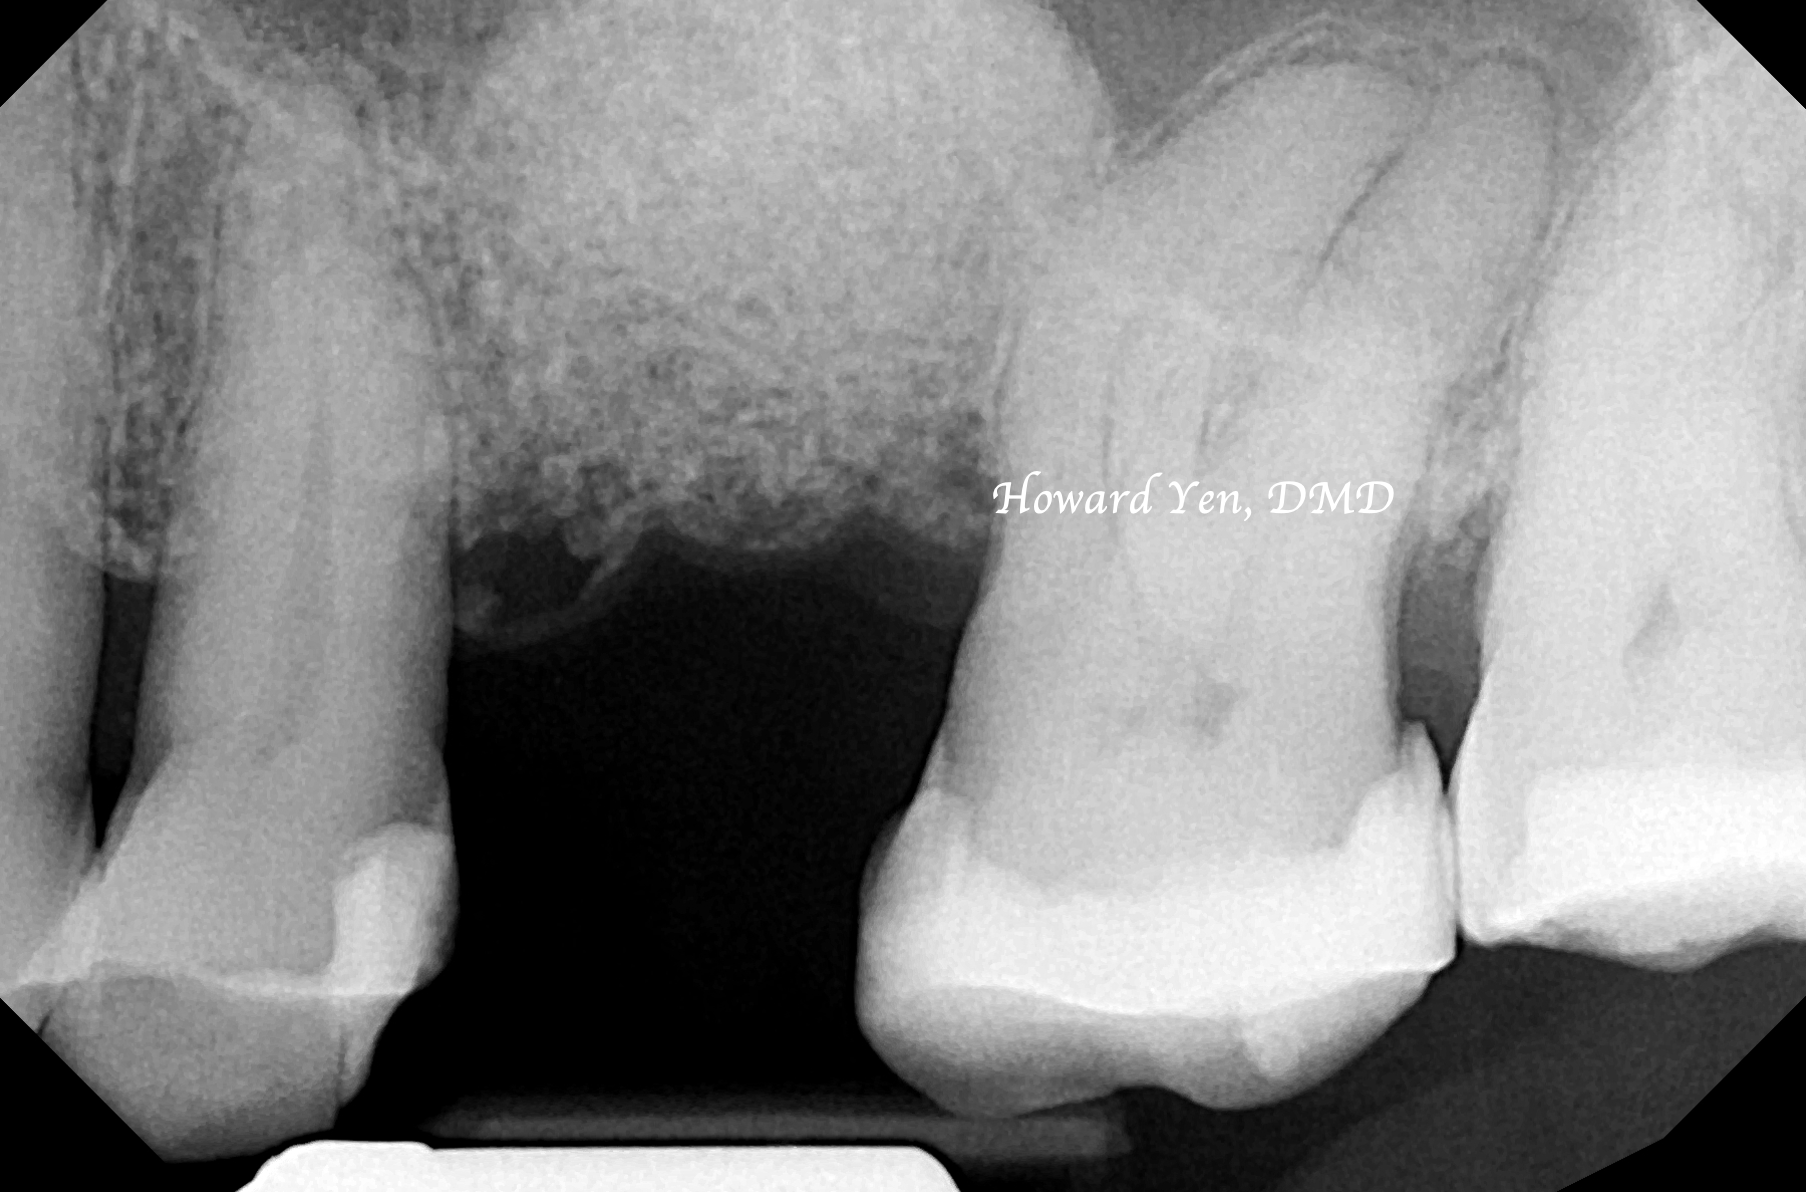

There’s the presence of maxillary sinus cavities around our nasal area and upper jaw bone. When an upper back tooth (molar or premolar) is removed, the sinus air cavity will quickly replace the jaw bone space once held by the roots of the molar/premolar. Some surgical interventions can be completed to help reduce the shrinkage of the bone volume or to help reconstruct/re-build the lost jaw bone volume around the sinus region to facilitate the placement of dental implants.